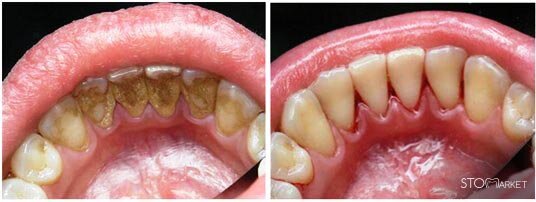

Зубной камень – это отвердевший налет (иногда он также называется зубная бляшка). Может быть наддесневым, тогда его можно увидеть невооруженным глазом, и поддесневым, в этом случае обнаружить его может только врач-стоматолог. Наиболее частая причина возникновения – неправильная или редкая чистка зубов. Налет образуется очень быстро, процесс запускается буквально через несколько минут после чистки. Минерализованные отложения – распространенная проблема, она наблюдается примерно у 90% пациентов стоматологических клиник. Обычно цвет отложений – желтый или коричневый, и проблема это не только косметическая, но и влекущая различные патологии (гингивит, кариес, кровоточивость десен, подвижность зубов, запах изо рта). Дети в меньшей степени подвержены этой неприятности, однако если вы заметили пожелтение зубов или ребенок жалуется на кровоточивость десен, лучше обратиться к врачу.

• Наддесневой. Чаще всего появляется на внутренней поверхности нижних зубов (в запущенном варианте переходит на внешнюю сторону), первых верхних моляров. Виден невооруженным глазом.